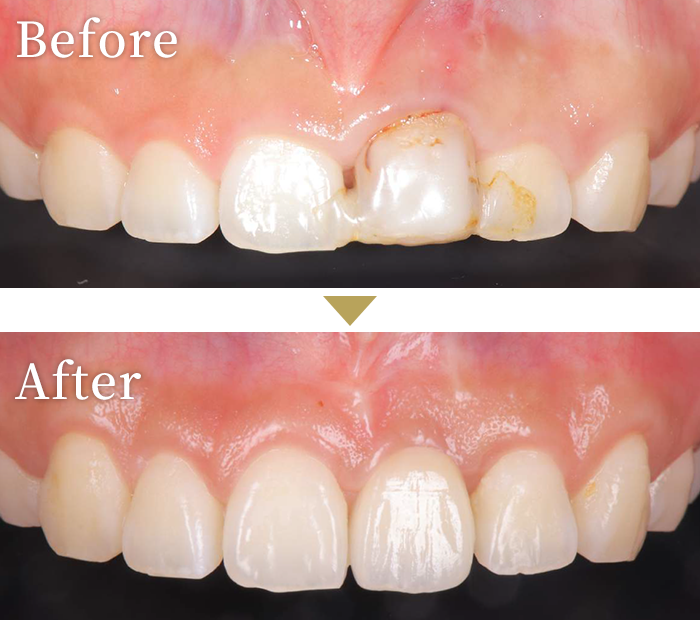

症例1

歯肉切開により

自然な口元を獲得した症例

インプラント症例1

主訴 幼少期にぶつけた前歯を綺麗にしたい

治療内容 左中切歯にインプラントを埋入し、セラミックの上部構造を装着。

左右対称性の獲得の為、審美性も考慮した治療を実施。

また、歯茎が分厚く、本来の見えるべき歯の形態見えていないため、インプラント治療とは別に歯肉切開を行い、歯牙本来の自然形態の獲得。※歯冠長延長術(=クラウンレングスニング)は、インプラント治療には含みません。

治療期間 約9ヶ月

標準費用

(自費)

約65万円

リスク

副作用

• 治療には必ず手術を伴います。

• 重度の歯周病がある場合は、インプラント埋入後、脱離のリスクが高いです。

• 体質等によりインプラントと骨の定着が困難な場合があります。